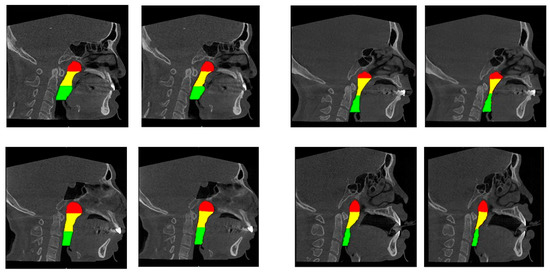

2.4.2. AI Segmentation Models

3.1. Accuracy Analysis for AI-Driven Upper Airway Segmentation

4.1. AI-Driven Segmentation Accuracy